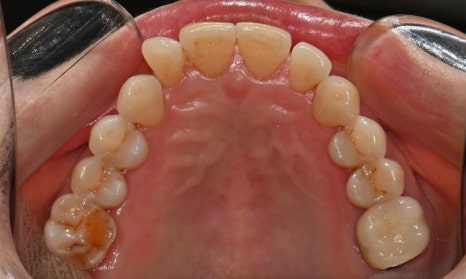

본 환자는 70세 여환으로 가만히 입을 다물고 있을 때 화난 것 처럼 보인다고 해서 튀어나온 앞니를 조금 넣고 싶다는 주소로 내원하셨습니다. 전체적인 치아 및 잇몸 상태를 검진해본 결과, 마모되어 깨진 치아도 있었고, 치경부(치아와 잇몸 사이 경계 부위)가 마모되어 파여 있는 부위도 많았습니다.

2025.2.3. 초진

교정 치료를 시작하기 전에 위아래 깨진 어금니는 보철 치료를 시행하였고, 치경부는 레진 치료를 시행하였습니다. 거의 뿌리의 신경관 근처까지 파여있던 치아가 치경부 레진 치료로 자연스럽게 수복이 되었습니다.

치경부 레진 치료 전후